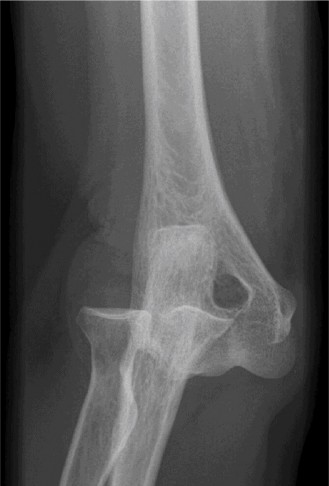

Imaging should include x-rays, which may demonstrate posterior glenoid bone loss or an impaction fracture on the anterior-superior humeral head (Fig. 2–38). CT images with 3D reconstructions can be very useful when assessing the extent of glenoid bone loss and evaluating glenoid and humeral version. Normal glenoid version is from −2 to −8 degrees of retroversion, and this may be increased in posterior instability. MRI can also be useful when assessing the posterior labrum (Fig. 2–39).

Figure 2–38 Radiographs showing a posterior shoulder dislocation.